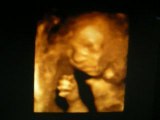

Dans la séquence qui suit on peut donc voir la petite regarder attentivement les photos, puis palper le ventre de sa maman qui va alors lui demander en langage des signes le sexe du bébé. La petite fille va répondre sûre d'elle que le bébé sera un garçon ce qui est bien le cas !